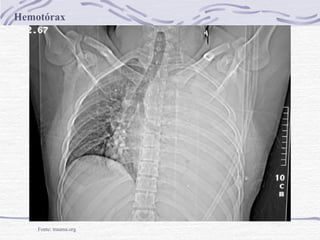

Hemotórax

Fonte: trauma.org